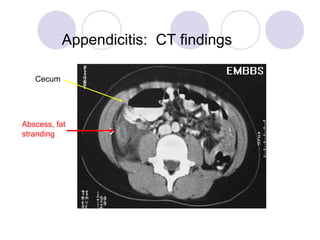

Appendicitis: CT findings

Abscess, fat

stranding

Cecum